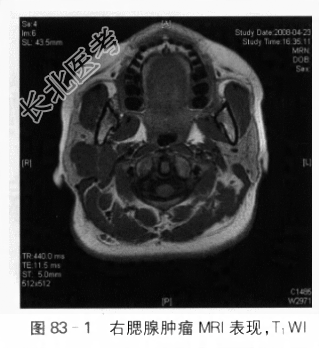

辅助检查:(1)B超检查提示右侧腮腺内见38mm×30mm低回声区,形态规则,边界清,内部回声欠均匀,血流信号少许,双侧腮腺切面形态大小正常,表面光滑,包膜完整,内部回声细小均匀。(2)MRI检查:右侧腮腺区见结节状肿块影,大小约3.7cm×3.2cm×2.4cm,形态不规则,部分伸入下颌后凹,边界尚清,T1WI呈略低信号(见图83-1),T2WI为高低混杂信号(见图83-2)。